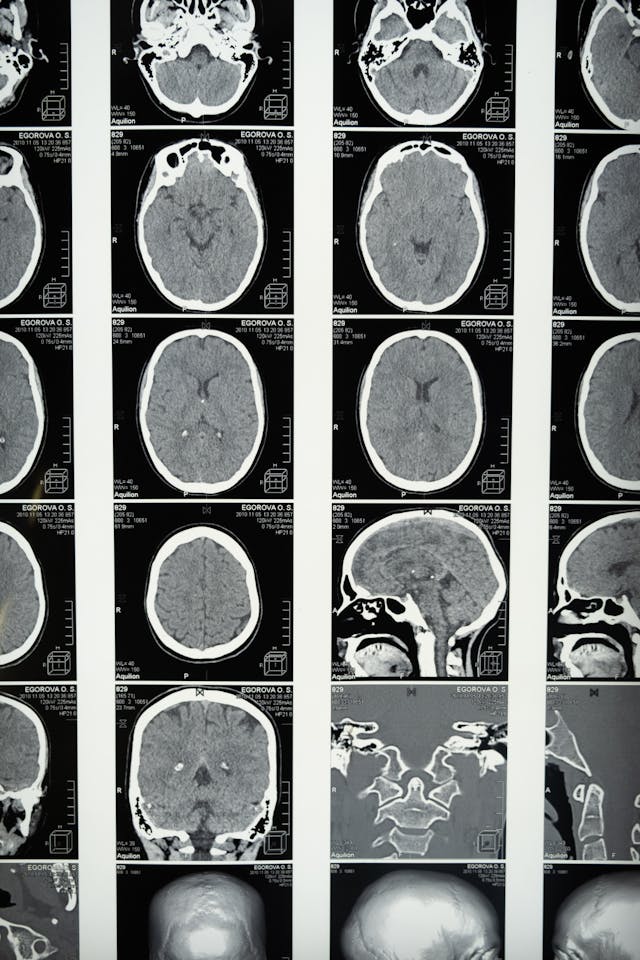

뇌혈관 사고(CVA)라고도 알려진 뇌졸중은 뇌로 가는 혈류가 방해되어 뇌세포 손상과 잠재적으로 생명을 위협하는 합병증으로 이어질 때 발생하는 의학적 응급 상황이다.

뇌를 공급하는 혈관이 막혀 발생하는 허혈성 뇌졸중의 경우, 치료는 혈전을 제거하기 위해 조직 플라스미노겐 활성제(tPA)와 같은 혈전을 파괴하는 약물을 투여하거나 기계적 혈전 절제술을 시행하는 것을 포함할 수 있다.

뇌에서 출혈로 인한 출혈성 뇌졸중의 경우, 치료는 손상된 혈관을 복구하는 수술 또는 출혈을 줄이고 더 이상의 합병증을 예방하는 약물을 포함할 수 있다.